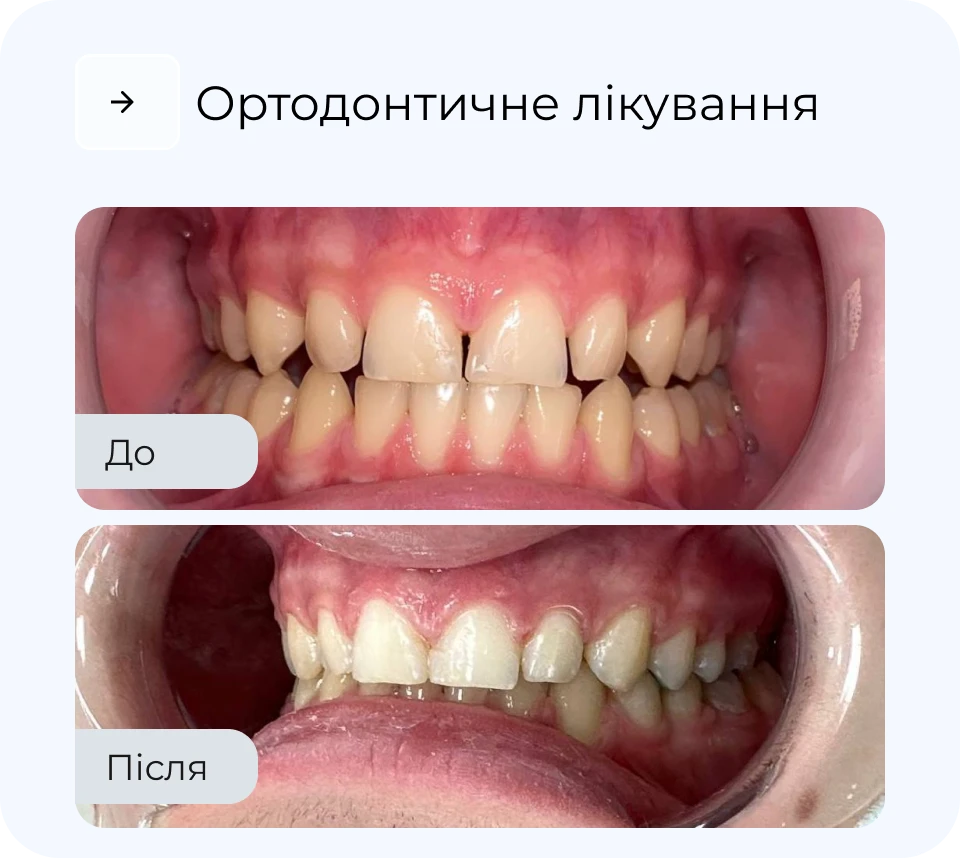

Ортодонтичне лікування дозволяє не лише вирівняти зуби, а й покращити функцію всього щелепного апарату. У MAXI Dent підбирають метод корекції індивідуально — від класичних брекетів до майже непомітних елайнерів. Процес лікування контролюється на кожному етапі, що забезпечує прогнозований результат. Наш підхід — максимально комфортно, естетично і без зайвих втручань.

Наші результати роботи

Результати

*тисни, щоб побачити до/після

Результати

*тисни, щоб побачити до/після